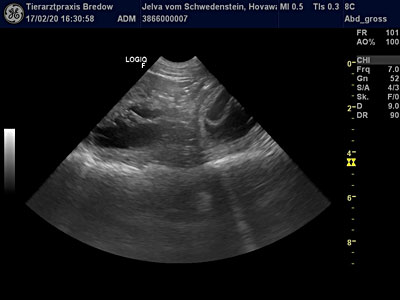

17.02.2020

30. Tag

"Ultraschall" |

Die Ungewissheit hat ein

Ende. Die heutige

Ultraschalluntersuchung bestätigte unsere Vermutung - Jelva ist tragend! Mehrere

Fruchtblasen mit ihren Föten konnten wir sehen - der L-Wurf ist im

Anmarsch. Jelva geht es sehr gut. Sie zeigt sich etwas ruhiger und

anhänglicher als sonst, aber ist wachsam wie eh und je! Sie wog heute beim

Tierarzt 32.2 kg - für Jelva Normalgewicht - also alles im grünen

Bereich.